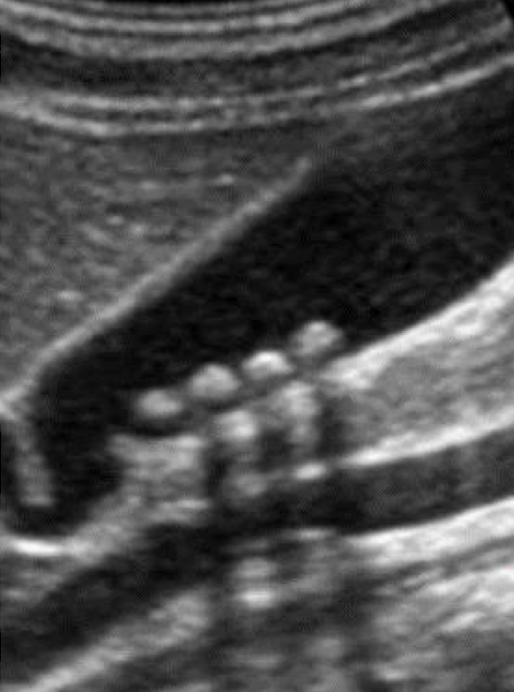

SONO: cholelithiasis

twinkle artifact

posterior shadow (due to refraction, impedance, intensity of the sound beam, and stone(s) size)

WES (wall echo shadow)

indicative of a stone-filled GB (GB is a packed)

3 arched-shaped line

shadow posterior to 3rd line

??

cholelithiasis

calcified stones with posterior shadowing